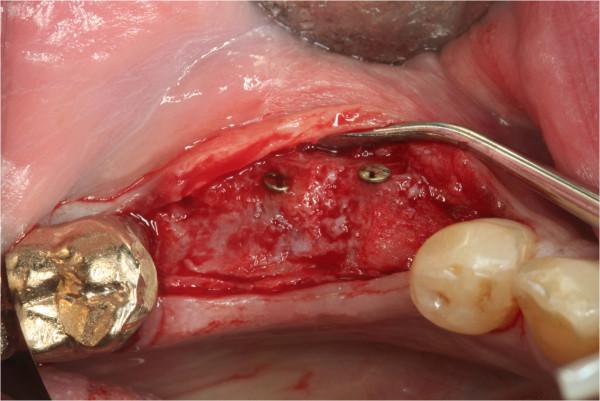

From 2003 to 2009, 67 patients underwent alveolar ridge augmentation and were enrolled in the study, 41 meet the inclusion criteria and 31 agreed to take part in the study. Patients were 18-69 years old (mean: 49.3 ± 13.8 years), and predominantly female. Patients received bone block grafts either autologous (n = 48) (AUBB) or allografts (ABB) (n = 19). Implants were inserted 4-7 months (autografts) or 5-6 months (allografts) after bone grafting. The Pink Esthetic Score (PES) as well as radiographic and subjective assessments were employed for the outcome analysis. The PES was assessed twice within one month based on digital photographic images that were randomly rearranged between evaluations by three independent, experienced investigators.

从 2003 年到 2009 年,67 名患者接受了牙槽嵴增高术,并被纳入研究,其中 41 名符合纳入标准,31 名同意参与研究。患者年龄 18-69 岁(平均:49.3±13.8 岁),主要为女性。患者接受骨块移植,自体(n=48)(AUBB)或同种异体(ABB)(n=19)。骨移植后 4-7 个月(自体)或 5-6 个月(同种异体)植入种植体。采用 Pink 美学评分(PES)以及影像学和主观评估进行结果分析。PES 在一个月内评估两次,根据数字摄影图像进行评估,评估之间图像随机排列,由三位独立、有经验的研究人员进行评估。